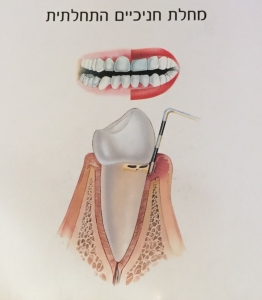

"סרגלון" דמוי מחט נכנס לאזור הכיס שבין השן לחניכיים ובעומק של מעל ל- 2 מילמטר מראה על מחלה.

"סרגלון" נכנס לעומק הכיס ומצביע על מחלת חניכיים מתקדמת.

בדרך כלל רופא החניכיים ולעיתים גם השיננית מבצעים בדיקה עם "הסרגלון" ורושמים בטבלה את עומק הכיסים ועל סמך המדידות קובעים את הטיפול המתאים

האבחנה בדבר קיומה של מחלת חניכיים ושלבי התקדמותה מתבצעת באמצעות מדידת כיסי החניכיים, מדדי דימום, רובד וצילומי רנטגן שאותם מבצע רופא השיניים או הפריודונט.